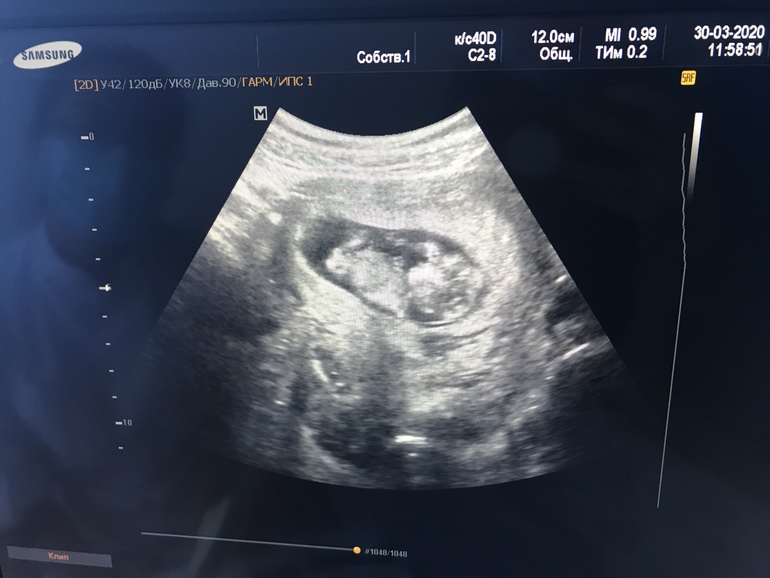

Как же быстро бежит время нам уже 12недель👼🙏🏻

Сегодня вновь встретились с малышом на узи❤️ Ну это просто крутыш, лежит подложив руку под голову 😍

Наконец-то я сегодня попала на Узи.

Боже какое же это счастье❤️ По Узи поставили 10+1, по месячным 11+3. Но у меня длинный цикл, овуляция поздняя.

Сказали все хорошо, лежит дёргает ножками, ручками❤️❤️❤️

Сердечко стучит 177 ударов в минуту.